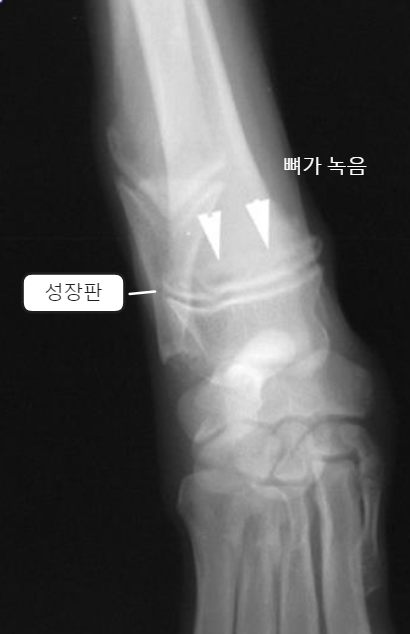

| - 아래쪽만 양옆으로 커지면서 flaring 양상을 보임. | Early sign - Metaphyseal soft tissue swelling | 비정상적인 periosteal reaction이 심하게 나타남, 성장판도 손상 받음 |